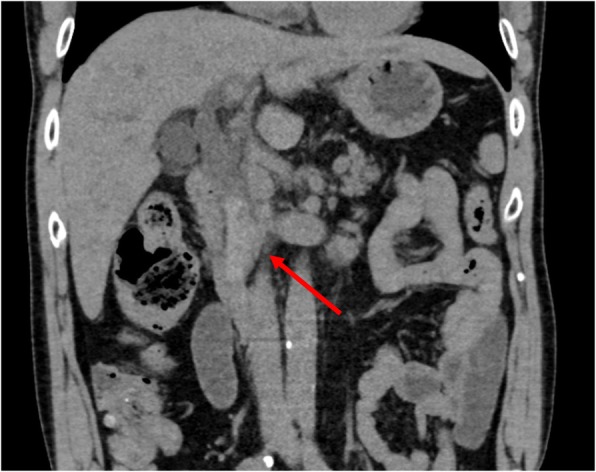

A 64-year-old man presented to our hospital with upper abdominal pain, jaundice, and anorexia. He had diabetes and was a social drinker but a lifetime non-smoker. Computed tomography (CT) scan revealed a dilated CBD, and acute cholangitis was suspected. The patient was referred to our hospital and admitted to the gastroenterology department for further investigation and treatment. Initial laboratory examinations revealed a white blood count (WBC) of 9770/μL, hemoglobin of 12.4 g/dl, increased C-reactive protein (CRP) of 5.47 mg/dl, total bilirubin of 7.75 mg/dl, AST/ALT of 176/281 IU/L, alkaline phosphatase of 815 IU/L, and ɤ-GTP of 132 IU/L. The serum tumor markers carcinoembryonic antigen (CEA) was within the normal range at 2.6 ng/ml and cancer antigen 19–9 (CA19–9) was elevated at 1162 U/ml. Both hepatitis B surface antigen (HBsAg) and antibodies to hepatitis C virus (anti-HCV) were negative. A plain CT scan on admission showed a high-density accumulation spreading throughout the CBD, and the entire CBD was dilated (Fig. 1). Gastroenterologists performed endoscopic retrograde cholangiopancreatography (ERCP) and endoscopic sphincterotomy (EST), during which a hematoma in the CBD was discovered. This revealed the reason for obstructive jaundice was not choledocholithiasis but the hematoma, which was subsequently drained through the incised Vater’s papilla (Fig. 2). A few days later, enhanced CT scan and magnetic resonance cholangiopancreatography (MRCP) were performed, and they showed improved dilation of the CBD and enhanced wall thickness of the bile duct measuring 25 × 10 mm at the union of the cystic and common hepatic ducts (Figs. 3 and 4). A cholangioscope detected an elevated tumor covered by sludge in the CBD (Fig. 5). The mucous membrane around the tumor showed redness and a malignant tumor was suspected. The result of the tumor biopsy revealed no malignant features in the histology, but the possibility of CC could not be denied from the macroscopic findings. We were consulted for surgical resection and performed an extrahepatic bile duct resection and cholecystectomy. Intraoperative rapid pathological diagnosis was performed, and we confirmed that the surgical margins in both the pancreatic and hepatic sides were cancer-free. The postoperative course was uneventful. The resected tumor had irregular elevated mucosa with an ulcerated lesion (Fig. 6a). The pathological examination of the resected tumor revealed that the ulcerated lesion had inflammatory granulation tissue; however, it did not contain the components of invasive carcinoma (Fig. 6b). Many consecutive intraepithelial micropapillary lesions spread around the ulcerated lesion, and the epithelial cells showed increased nucleus-to-cytoplasm ratio, nuclear hyperchromasia, and architectural atypia (Fig. 6c). The pathological diagnosis was BilIN-1 to -2. It also revealed that the BilIN-1 lesion spread through both the pancreatic and hepatic margins. Immunohistochemical staining showed that S100P was slightly expressed in the cytoplasm and MUC5AC was positive, while MUC1 was negative and p53 was not overexpressed (Fig. 6d–g).